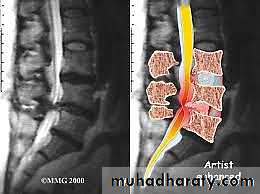

MRI

It is superior to computed tomography (CT) because of its tissue contrast and multi planar capabilities.General objectives of treatment